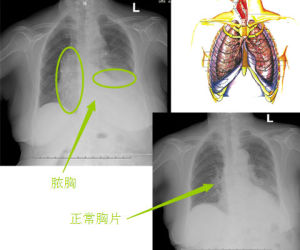

患者體溫高,呈弛張熱。白細胞計數增高,中性粒細胞增至80%以上,細胞核左移。胸部X線檢查

急性膿胸中等量積液時,X線顯示下胸部外高內低的弧形緻密積液影,陰影遮蓋整個膈面,積液量約500~1000ml。

大量積液時液體可達肺尖,肺組織受壓萎縮,患側透過度進一步減低,胸腔體積增大,肋間隙變寬,肋骨位置變平,縱隔向健側移位,橫膈下降,在左側由於胃泡內空氣的對比容易顯示,在右側由於肝臟與積液密度相近,故不易分辨。

合併膿氣胸或支氣管胸膜瘺時,可見到液氣面。

局限性膿胸多見於胸腔的後壁及側壁,X線可見到局部密度增高影,在其中央部分密度較深,周圍漸淺,在切線位上表現為貼於胸壁的局奶性的密度均勻的陰影,基底部較寬,內緣清晰,呈扁平狀或半圓形突向肺野,也可表現為葉間積液、肺底積液、縱隔積液等,常需與胸膜病變、肺部腫瘤、膈下膿腫、肝膿腫鑑別。常需與胸膜病變、肺部腫瘤、膈下膿腫、肝膿腫鑑別。